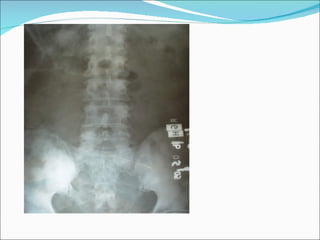

17. PROSTATE CANCER Distant metastatic spread Lung Bone Liver Epidural space